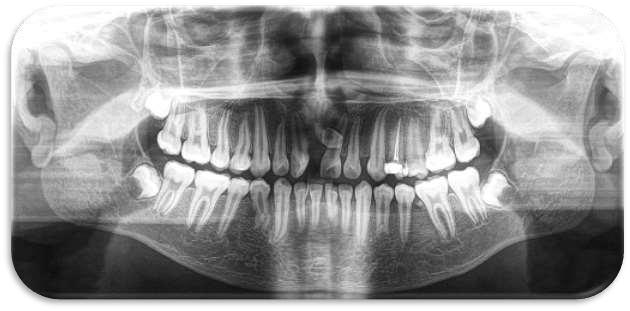

La ortopantomografía revela:

Dos supernumerarios de morfología cónica en la región interincisal superior

Ambos mesiodens erupcionados, en coexistencia con los incisivos centrales permanentes.

Ausencia de patología periapical o lesiones radiolúcidas asociadas

Pieza 2.1 y 1.1. 2.2 1.2 con mesioversion

Presencia germen dentario piezas 8

Doble mesiodens erupcionado en región anterosuperior, coexistiendo con incisivos centrales permanentes erupcionados y sin diastema.